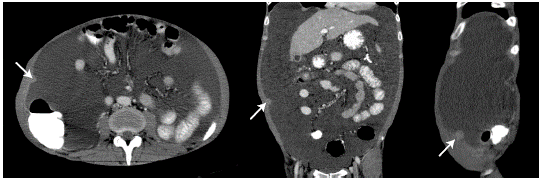

On physical examination, the patient was in poor general condition, tachycardic, normotensive, afebrile and with cachexia; his weight was 48kg, and he presented with distended abdomen with shifting dullness, cardiopulmonary auscultation without alterations, positive ascitic wave and pain on palpation without signs of peritoneal irritation, and peritoneal dialysis catheter without local inflammatory signs. A computed tomography (CT) of the abdomen was performed, showing a single nodular image of well-defined edges, with soft tissue density, of 12mm in diameter, located in the peritoneal plane of the right abdominal wall and associated with abundant ascites of free characteristics, splenomegaly and slight thickening of the parietal peritoneum (Figure 1 and 2).

CT scan of the abdomen, axial, coronal and sagittal planes, showing nodular lesion (arrow) in the parietal peritoneum.

Figure 1: CT scan of the abdomen, axial, coronal and sagittal planes, showing nodular lesion (arrow) in the parietal peritoneum.

Source: Document obtained during the study.

In diagnostic imaging, PH is characterized by diffuse nodular thickening of peritoneal surfaces that have soft tissue attenuation on CT and are enhanced by intravenous contrast administration. Other findings may include ascites, hepatic or splenic microabscesses of miliary distribution, peritoneal or hepatic granulomas, and diffuse striation of the omentum or mesenteric fat. 12,13

Finding disseminated peritoneal lymph-adenopathies or nodules is highly relevant as they suggest peritoneal involvement secondary to hematogenous dissemination. 13 Gastrointestinal involvement (thickening of the terminal or blind ileum) by histoplasmosis suggests dissemination by contiguity secondary to intestinal microperforations. PH is included in the spectrum of granulomatous peritonitis and, therefore, its imaging characteristics are indistinguishable from peritoneal tuberculosis infection. 12